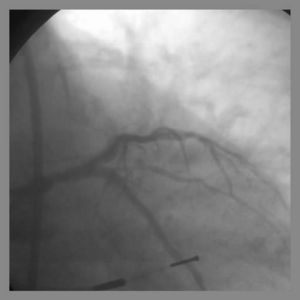

T-Stenting

Detriments:

Very difficult, if not impossible to completely cover side branch ostium Requires final kissing balloon inflation Modified T-stent technique requires 7Fr guide system

May use a 6Fr Guiding system Final Kissing balloon inflation required due to high Restenosis rate Ideal angle of bifurcation is at or near 90 degrees.